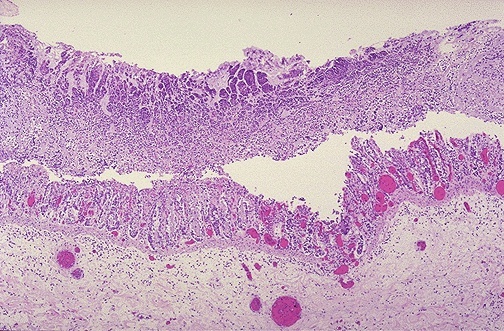

How do you get this infection?

Prior antibiotic use

(Note the pseudomembrane over the colonic mucosa)

In which patients would this complication occur?

Immunocompromised and chronic liver disease patients